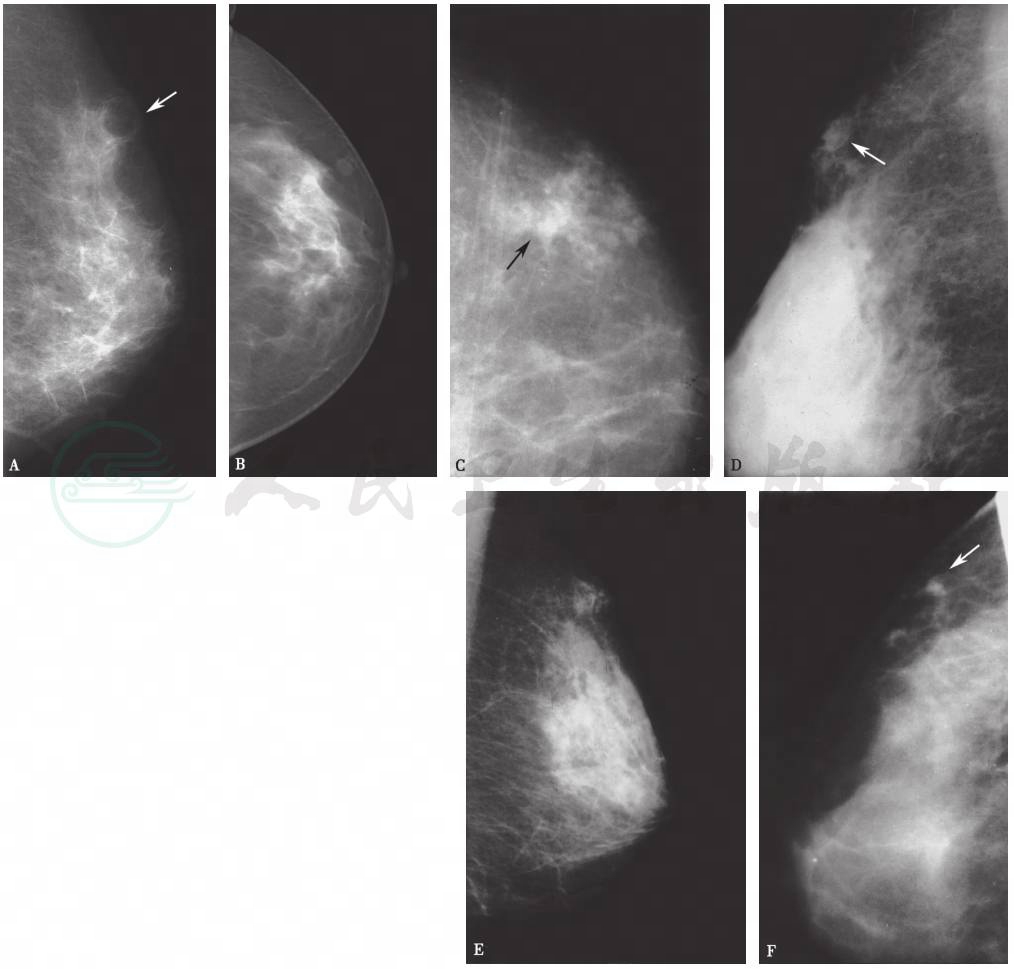

有研究将脂肪坏死分为超急性炎性期、急性炎性期、脂质囊肿期、炎性肉芽肿期,不同时期的病理改变不同,脂肪坏死的X线表现亦不相同(图1)。病变早期,脂肪组织被酯酶溶解液化,表现为孤立的脂肪性小叶(脂性囊肿),病变组织与正常的脂肪组织均表现为低密度,其间尚未形成纤维结缔组织,此时可无异常X线表现。随着病变的发展,液化、坏死的脂肪周围形成结缔组织、钙化,包绕液化坏死的脂肪形成“囊肿”。乳腺X线摄影主要表现为乳后脂肪间隙及腺体周围脂肪层内多发、边缘清晰的薄壁脂肪密度或结节状等密度病灶,密度较均匀。随着病变进展,脂肪坏死X线表现为不规则致密结节和肿块、局限性非对称性致密,病变与邻近的腺体无关;也可以表现为病变处结构扭曲,偶尔可见病变表现为油脂囊肿或伴有脂滴样钙化或斑片状钙化。油脂囊肿(伴或不伴囊壁钙化)是脂肪坏死的唯一特异性X线表现。腺体内型脂肪坏死有时因缺乏特异性的X线表现容易误诊为乳腺癌。在多种X线表现中,皮下脂肪层内索条状、星芒状、网状影与腺体内脂性囊肿属于乳腺脂肪坏死的典型表现。

图1脂肪坏死在乳腺X线摄影上的不同表现

A.脂肪坏死所致脂性囊肿,外上脂肪层可见囊性透亮区,囊壁较厚,边缘清楚锐利;B.结节型脂肪坏死,外侧脂肪层可见边缘光滑结节,周围伴斑片状致密影;C~F.脂肪坏死所致局限性结构不良(星芒状、斑片状、索条影及网状结构)、脂肪层混浊(内见斑片状致密影)